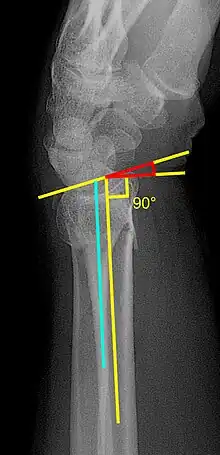

X-ray of the affected wrist is required if a fracture is suspected. Posteroanterior, lateral, and oblique views can be used together to describe the fracture.[5] X-ray of the uninjured wrist should also be taken to determine if any normal anatomic variations exist before surgery.[5]

Various kinds of information can be obtained from X-rays of the wrist:[5]

Lateral view

- Carpal malalignment - A line is drawn along the long axis of the capitate bone and another line is drawn along the long axis of the radius. If the carpal bones are aligned, both lines will intersect within the carpal bones. If the carpal bones are not aligned, both lines will intersect outside the carpal bones. Carpal malignment is frequently associated with dorsal or volar tilt of the radius and will have poor grip strength and poor forearm rotation.[5]

- Tear drop angle - It is the angle between the line that pass through the central axis of the volar rim of the lunate facet of the radius and the line that pass through the long axis of the radius. Tear drop angle less than 45 degrees indicates displacement of lunate facet.[5]

- Antero-posterior distance (AP distance) - Seen on lateral X-ray, it is the distance between the dorsal and volar rim of the lunate facet of the radius. The usual distance is 19 mm.[5] Increased AP distance indicates the lunate facet fracture.[8]

- Volar or dorsal tilt - A line is drawn joining the most distal ends of the volar and dorsal side of the radius. Another line perpendicular to the longitudinal axis of the radius is drawn. The angle between the two lines is the angle of volar or dorsal tilt of the wrist. Measurement of volar or dorsal tilt should be made in true lateral view of the wrist because pronation of the forearm reduces the volar tilt and supination increases it. When dorsal tilt is more than 11 degrees, it is associated with loss of grip strength and loss of wrist flexion.[5]

Posteroanterior view

- Radial inclination - It is the angle between a line drawn from the radial styloid to the medial end of the articular surface of the radius and a line drawn perpendicular to the long axis of the radius. Loss of radial inclination is associated with loss of grip strength.[5]

- Radial length - It is the vertical distance in millimetres between a line tangential to the articular surface of the ulna and a tangential line drawn at the most distal point of radius (radial styloid). Shortening of radial length more than 4mm is associated with wrist pain.[5]

- Ulnar variance - It is the vertical distance between a horizontal line parallel to the articular surface of the radius and another horizontal line drawn parallel to the articular surface of the ulnar head. Positive ulnar variance (ulna appears longer than radius) disturbs the integrity of triangular fibrocartilage complex and is associated with loss of grip strength and wrist pain.[5]

Oblique view

- Pronated oblique view of the distal radius helps to show the degree of comminution of the distal end radius, depression of the radial styloid, and confirming the position the screws at the radial side of the distal end radius. Meanwhile, a supinated oblique view of shows the ulnar side of the distal radius, accessing the depression of dorsal rim of the lunate facet, and the position of the screws on the ulnar side of the distal end radius.[5]